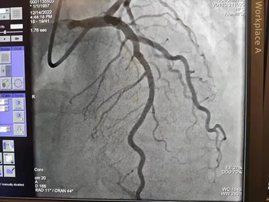

心血管造影

术后